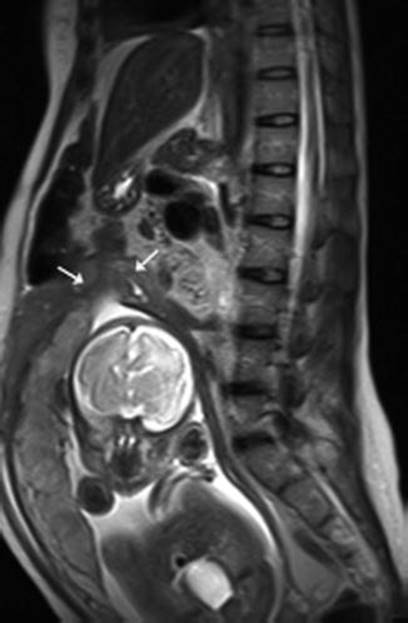

16.7.3 Magnetic Resonance Imaging

The MRI appearance consists of a focal myometrial defect which may be filled with hematoma and an associated hemoperitoneum (Fig. 16.13). Uterine rupture is a surgical emergency, and MRI should only be considered when the diagnosis is inconclusive and the patient is hemodynamically stable [212].

Fig. 16.13

A 35-year-old female patient in her third trimester with lower abdominal pain and with prior history of Cesarean delivery. Sagittal T2-weighted image shows a focal disruption at the fundus of the uterus (arrows) with associated hematoma. No part of the fetus protruded into the abdominal cavity [211]